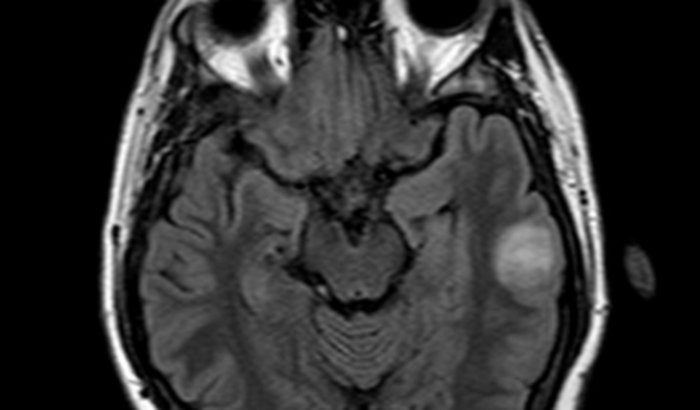

No dia 13 de dezembro tive uma convulsão. Fui encaminhado para o hospital, onde realizei exames de Tomografia e Ressonância Magnética. Após a investigação descobrimos que a convulsão foi causada por um Tumor cerebral na área esquerda, próximo a área da fala. Por conta disso, o procedimento cirúrgico que preciso realizar deve ser feito acordado e com urgência, o que justifica o alto custo da cirurgia.